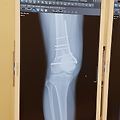

거대세포종 위치와 수술부위는 아래와 같구요...

골시멘트채우고 뼈강도 보강을 위해 철판을 댔다고 합니다.